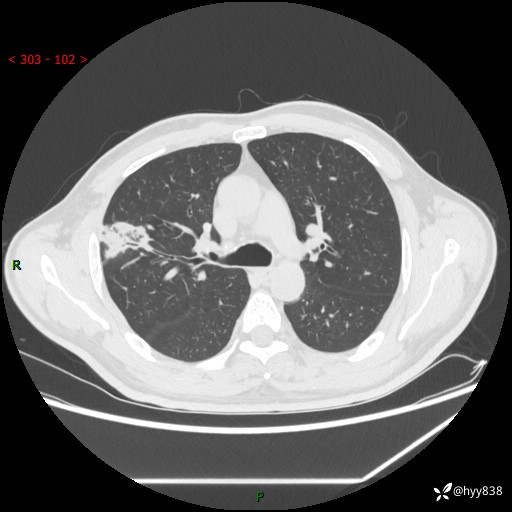

中年男性,体检发现肺占位2天。节段性实变,蜂窝样改变---结果公布~

现病史:患者2天前体检完善胸部CT提示:右上肺团块影,炎症可能,肿瘤性病变不除外,冠状动脉钙化,无咳嗽、咳痰,无寒战发热,无恶心、呕吐等其他特殊不适,未予以特殊治疗,现为明确病变性质来我院就诊,门诊以“肺肿物性质待查”收入我科。 起病以来,患者精神、饮食、睡眠可,大小便正常,体力体重较前无明显变化。

胸部CT平扫+增强